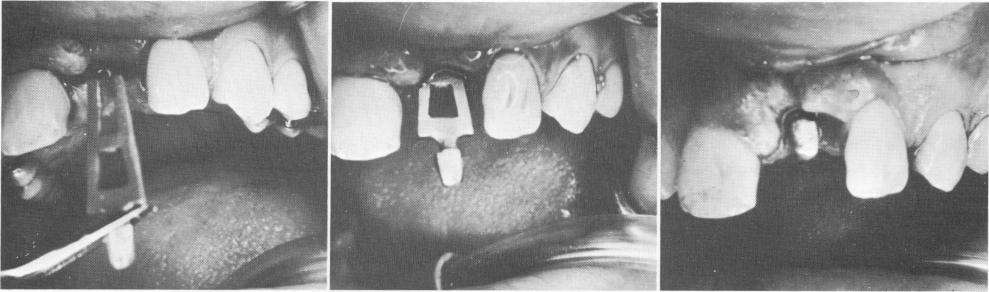

mucosal tissue was incised and reflected to expose the underlying bone, which was grooved with the No. 700L tapering fissure bur. Because the single tooth blade is much longer than usual (Fig. 11-28), the groove was made 9 to 10 mm. deep (Fig. 11-29). This was done so that only a small amount of force would be necessary to tap the implant to its proper depth. The blade was then carefully tapped into position (Fig. 11-30). After the tissue had completely healed, an impression for the crown was taken with elastic.

Fig. 11-28. A facial and profile view of the single tooth blade. Note length.

Fig. 11-29. A deep groove is made in the bone.

Fig. 11-30. Inserting the implant.

1 Facial and profile view of single tooth blade implant

2 Deep groove made in maxillary bone for bladevent insertion

3 Pictures showing insertion of blade implant in upper jaw